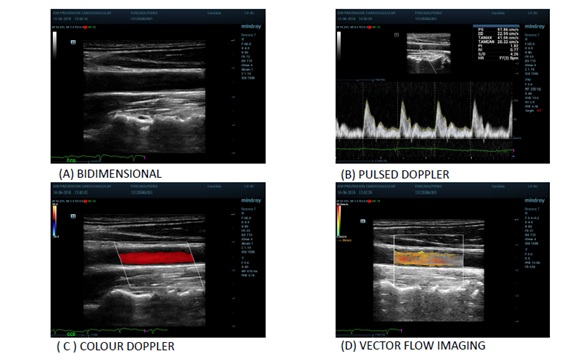

V Flow detects the speed and direction of all blood cells flowing through every point of the Region of Interest (ROI). There are low-speed cells, high-speed blood cells, and reversecells flowing through a point in a short moment. It means that the speed measured and displayed by V Flow in a point is the average speed of all blood cells in a precise short moment. Spatiotemporal characteristics of flow was evaluated visually and quantitatively to asses the specific flow patterns. VFI shows velocity vectors, streamline distribution and vorticity distribution. (Figure 2).

Figure 2: Vector flow imaging.

The streamline distribution uses arrows to indicate the flow direction. The colour and length of the arrows showed the flow velocity, magnitude and direction (green means low velocities, yellow and orange medium velocities and red higher velocities; the longer the arrows the faster the flow). For quantitative evaluation, velocity curves were available: the maximum velocity vector point curve, automatically detected by the system, and the user-defined vector point curve. Both were displayed at the bottom of the image and showed the fluctuating velocities of the flow varying in subsequent cardiac cycles (Figure 3) [12].

Figure 3: Different parameters obtained with vector flow imaging.